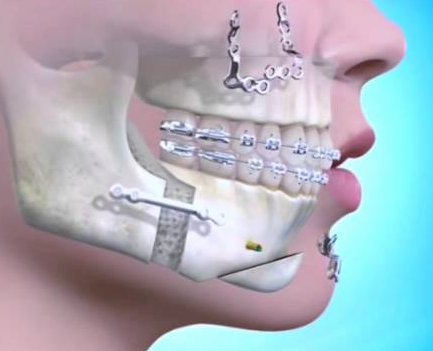

- Bimax (bimaxillary osteotomy) involves repositioning two jaws — the upper (maxilla) and lower (mandible) — to correct bite issues, facial imbalance, or airway problems.

Bimax involves repositioning both the maxilla (upper jaw) and mandible (lower jaw).

3. Custom Jaw Surgery vs Traditional Jaw Surgery

- Custom / 3D Bimax / Trimax (usually done at private clinics) : Uses virtual planning and custom titanium plates for perfect symmetry and aesthetic refinement.